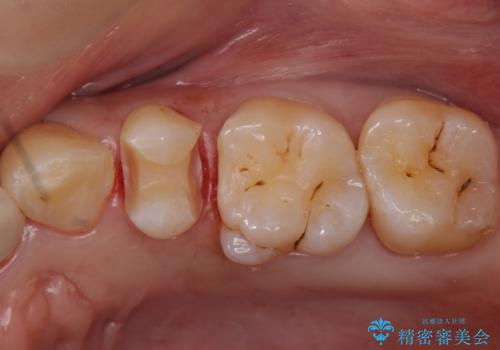

銀の詰め物を白くしたい セラミックインレーでの治療

- 銀歯が気になるためやり替えたいとのことで来院されました。

セラミックインレーで治療を行いました。

- 左上5 セラミックインレー 77,000円費用は治療当時の料金となります